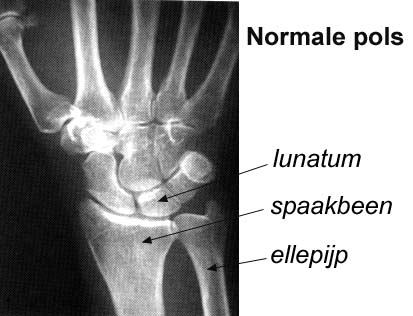

De ziekte van Kienböck is een aandoening in de hand waarbij het lunatum (het halve maanvormige botje) een van de 8 botjes in de handwortel is aangedaan (fig 1). De ziekte werd voor het eerst in 1910 in Wenen beschreven door een radioloog Robert Kienböck. Het lunatum vormt samen met het erboven liggende capitatum botje de centrale as van de handwortel. De aandoening komt meestal voor bij mannen tussen de 20 en 40 jaar.

Oorzaken kunnen zijn een afwijking in de aanleg van de normale bloedvoorziening en bloedvaten naar het lunatum. Daardoor wordt dit kwetsbaarder bij acute of chronische letsels en beschadigingen. Opvallend is dat we vaak het beeld zien dat in het polsgewricht de lengte van de ellepijp een stukje korter is dan van het spaakbeen (fig 2), de zogenaamde “ulna minus variant”. Het idee hierachter is dat bij deze variant de druk op het lunatum groter is dan bij een gelijke lengte. Andere mogelijke oorzaken zijn jicht, cortison gebruik, sikkelcel ziekte ed.